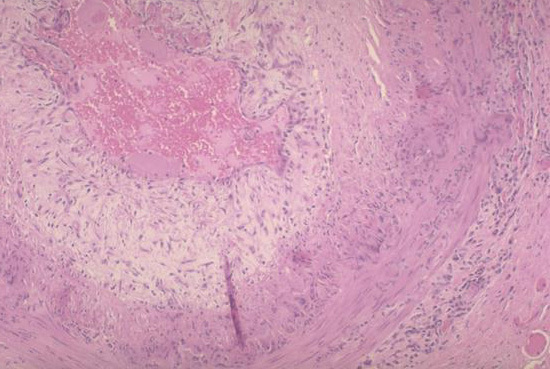

This disease may cause visual loss, jaw claudication (pain due to ischemia) and scalp tenderness - histo looks like this:

Giant cell arteritis